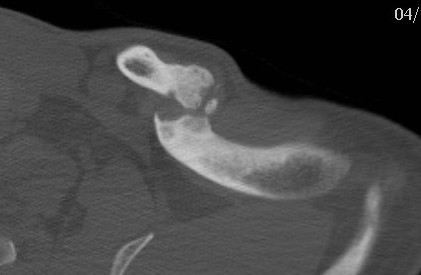

CT scan: green circle - clavicle nonunion, red arrows - subclavian artery, blue arrow - subclavian vein

Subclavian vein injury

Subclavian vein may be adhered to periosteum medially

- instrumentation medially and inferiorly must be subperiosteal

- careful with medial screws